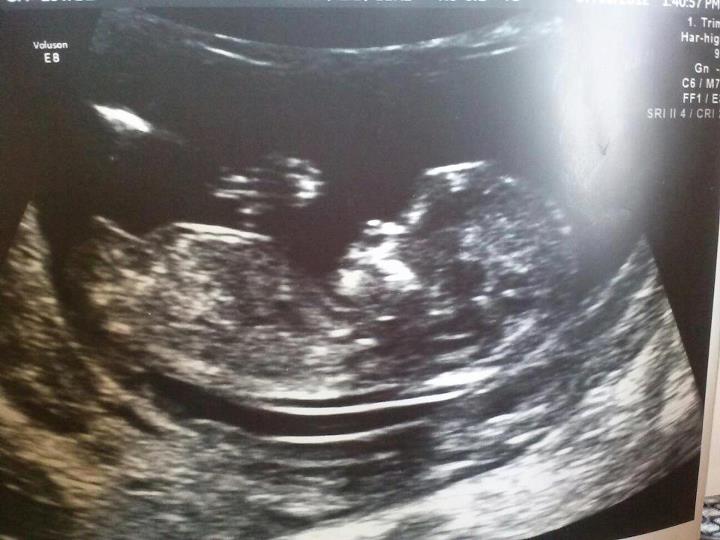

Attachment 4058Attachment 4059Attachment 4060please tell what you think im going nuts! Lol thanx in advance :)

ITS A GIRL!! confirmed at 18weeks and 6days... im now 23weeks and 6days and im super excited!!!!!